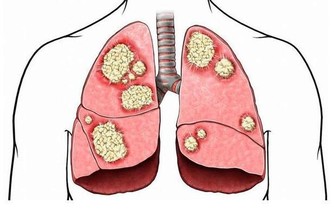

收治個案的台北市立聯合醫院仁愛院區心臟血管內科主治醫師林中行指出,該患者接受心臟超音波檢查發現,有嚴重心臟衰竭狀況,於是裝上葉克膜,主動脈氣球幫浦,接著做心導管檢查,發現所有冠狀動脈嚴重血管痙攣,但使用血管擴張劑後痙攣消失,僅有左前降支有50%的狹窄,之後轉進加護病房接受藥物治療與詳盡評估檢查。

林中行表示,根據研究顯示,容易冠狀動脈痙攣者,也有較高的支氣管敏感性。推測患者可能使用治療氣喘用的支氣管擴張劑,含有交感神經乙型受器促進劑的成份,容易引起心跳快、心肌缺氧、心律不整等副作用,使心絞痛發作時的病情雪上加霜。